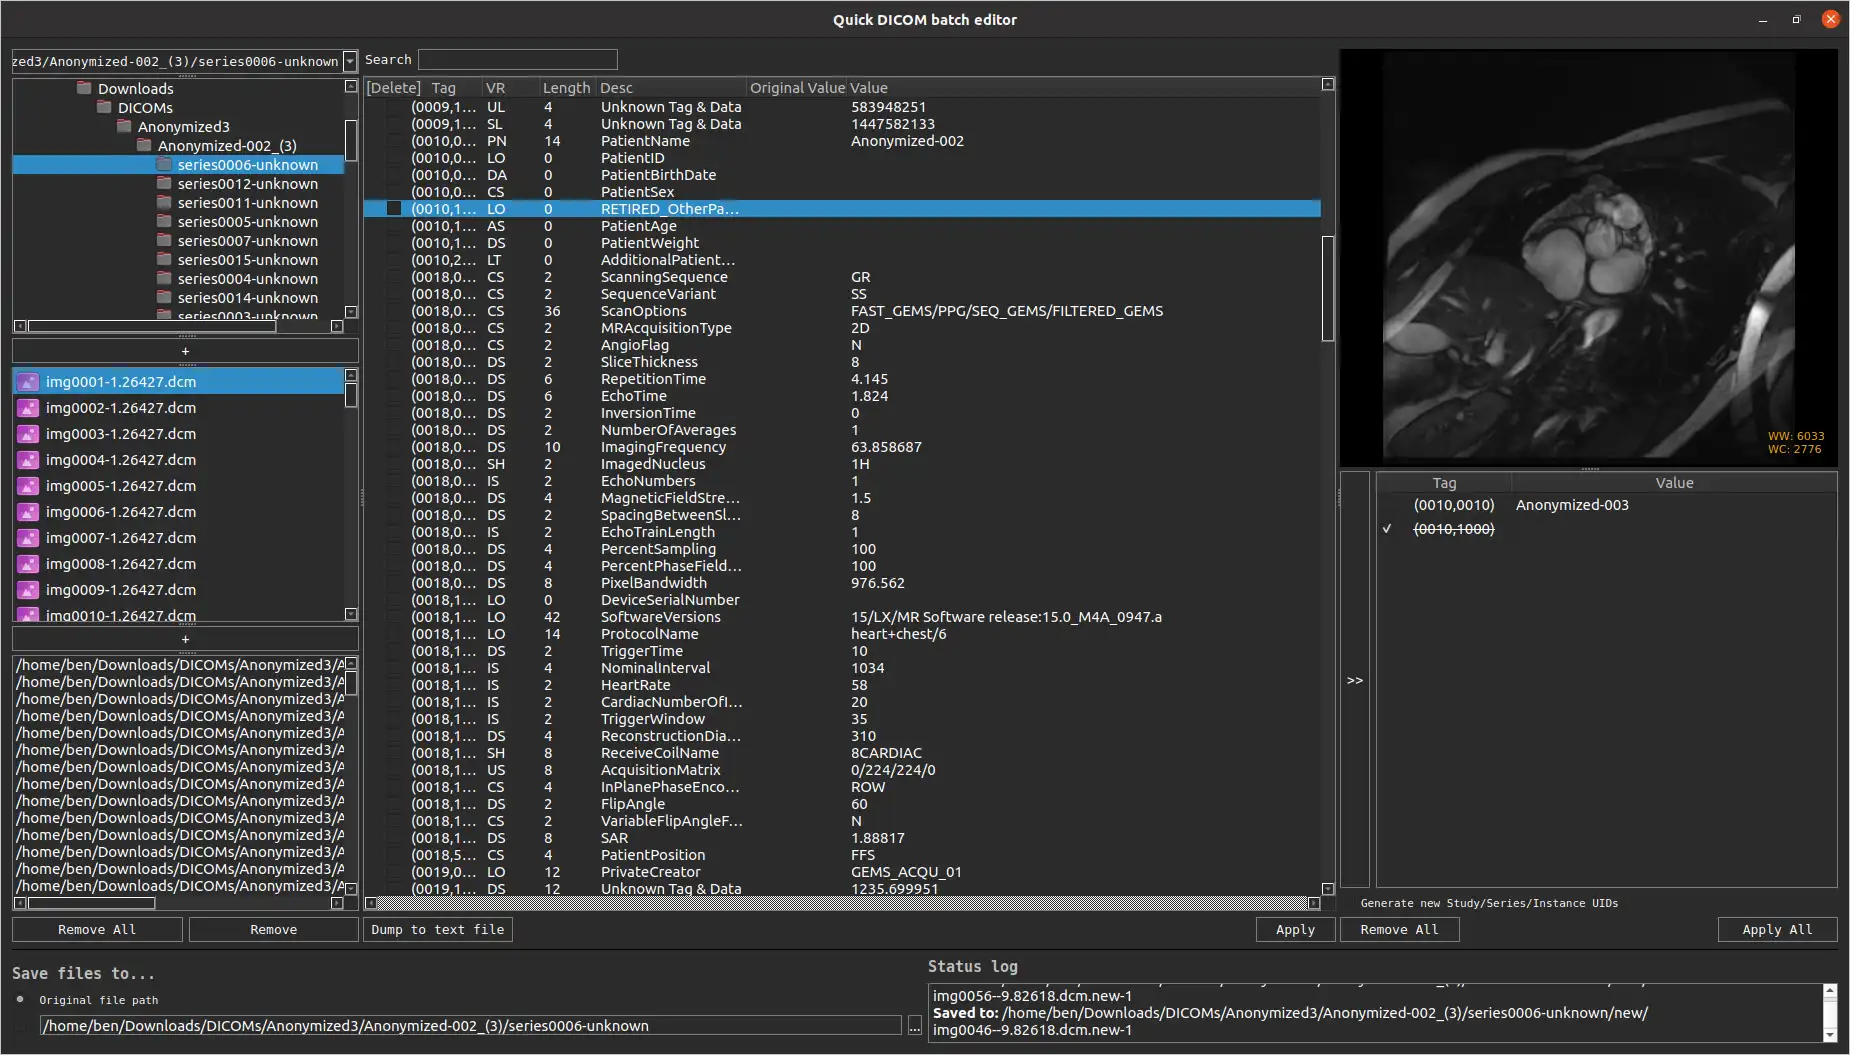

SCREENSHOTS

* Descrição geral

- Ver e modificar tags DICOM de um único arquivo

- Visualize e modifique as tags DICOM de vários arquivos

- Despeje as tags DICOM em um arquivo de texto

- Imagens de visualização (dados de pixel DICOM)

- Visualize e modifique as tags DICOM de um único arquivo

- Visualize e modifique as tags DICOM de vários arquivos

- Despejar tags DICOM em um arquivo de texto

- Imagens de visualização (dados de pixel DICOM)

- Plataforma cruzada - Windows, Mac, Linux